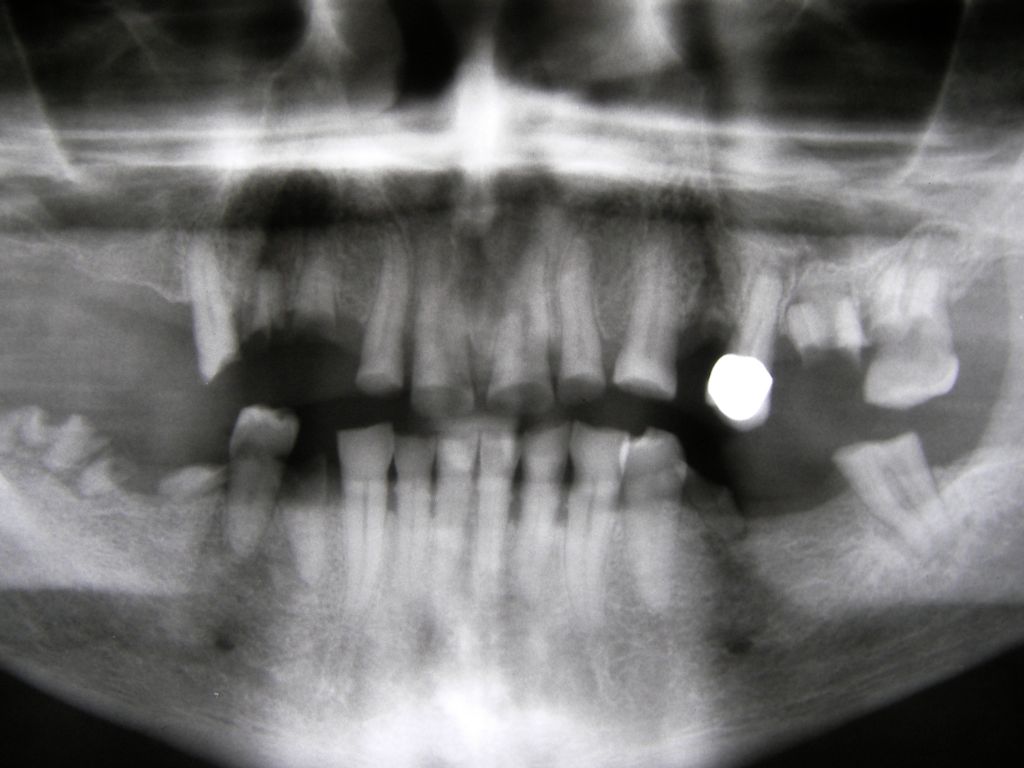

Besonderen Spaß macht mir großer, kombiniert festsitzend-herausnehmbarer Zahnersatz (sogenannter Kombi-Ersatz), auch mit Implantaten, weil er interessante Herausforderungen an den Behandler stellt. Diese Behandlungen sind oft langwierig, weil ein Behandlungsschritt auf dem anderen aufbaut: Häufig Parodontaltherapie, Wurzelkanalbehandlungen, Füllungstherapie, Implantate, erst am Ende Zahnersatz. Ob der Fall zur Zufriedenheit des Patienten gelöst werden konnte, stellt sich dann oft erst nach Monaten heraus. Hier ein einfacher Fall, bei dem keine besondere Vorbehandlung notwendig war. Der Patient, 58jährig, suchte die Praxis erstmals im September 2005 auf. Es erfolgten mehrere prothetische Planungen, der Gutachter des "Medizinischen Dienstes der Krankenkassen" (MDK) wurde noch von der Krankenkasse in Anspruch genommen, was heute bei größeren Planungen der Regelfall geworden ist. Umgesetzt wurde dann eine für einen solch großen Fall preisgünstige Lösung von 6434 Euro Gesamtkosten (4264 € Laborkosten, 2170 € Honorar). Die Krankenkasse übernahm als Festzuschuß 3843 €, für den Patienten verblieben 2591€. Im Januar 2006 ging es dann endlich los - zunächst allerdings beim Kieferchirurgen, weil wegen einer erhöhten, medikamentös bedingten Blutungsneigung es sicherer erschien, einige Zahnentfernungen von diesem durchführen zu lassen. Ausgangsbilder:

OPG aus 10/2003